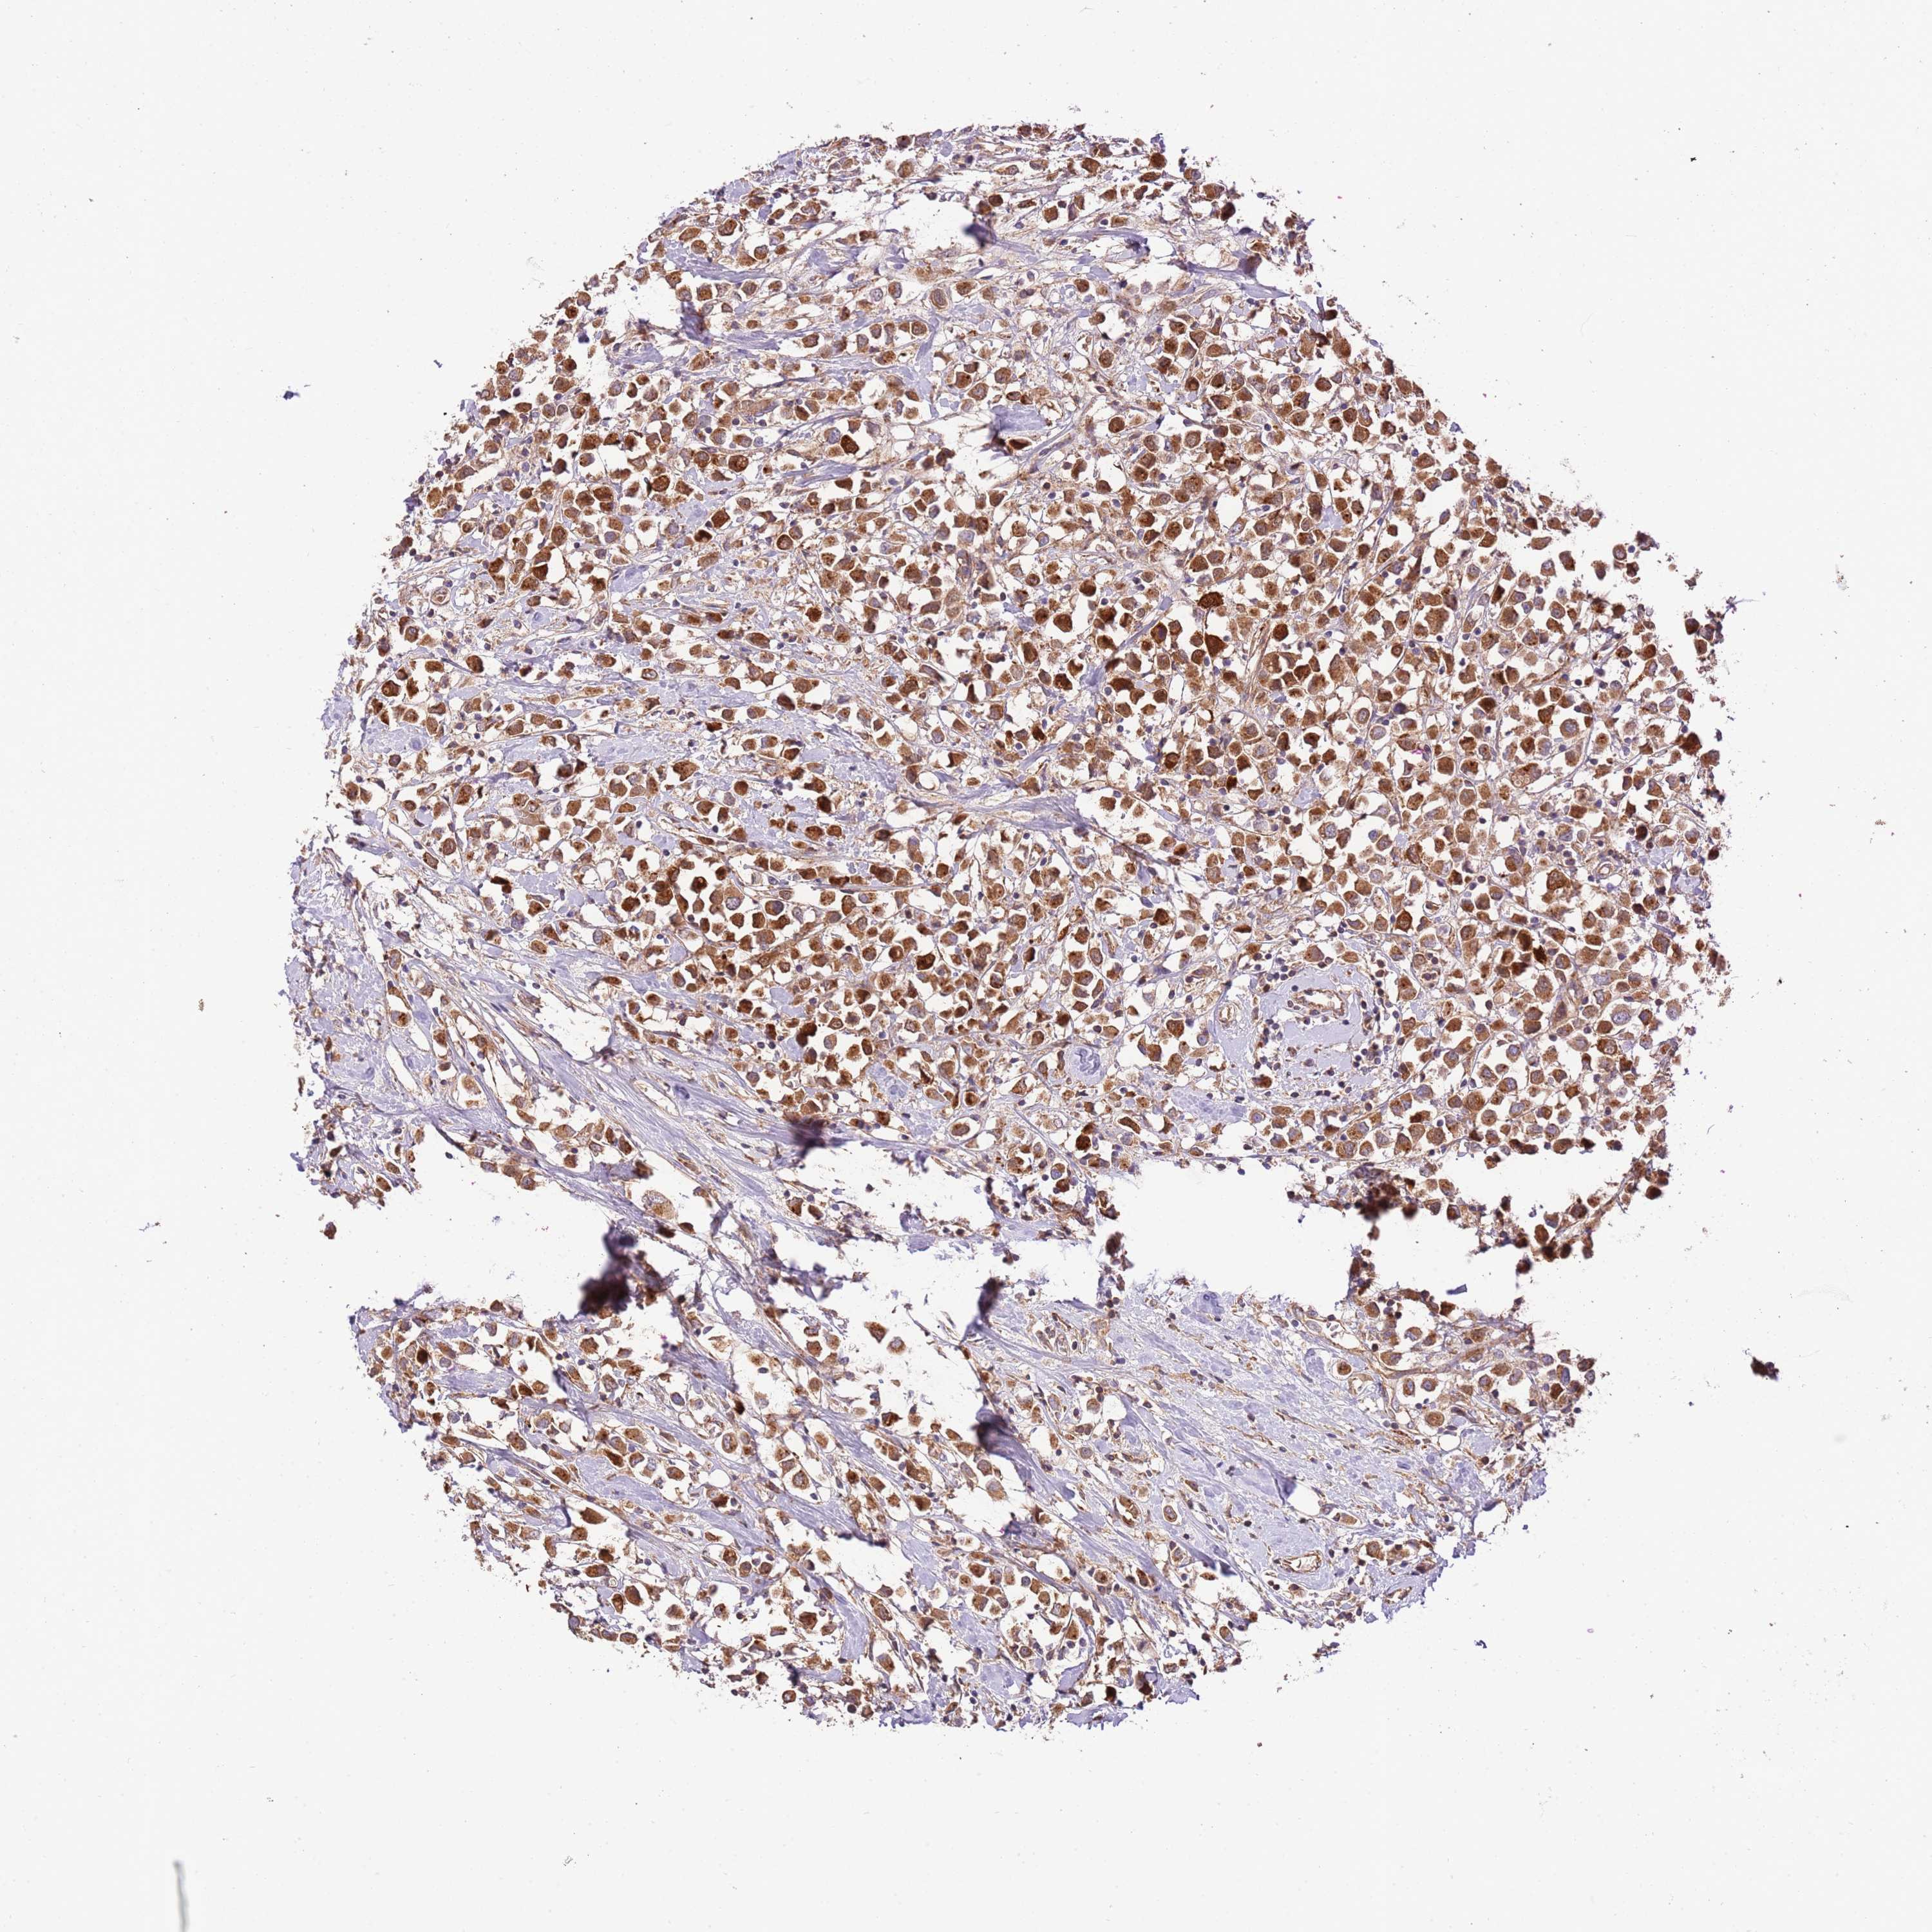

CANCER BREAST CANCER Show tissue menu

BRCA TCGA BRCA VALIDATION PROTEIN EXPRESSION